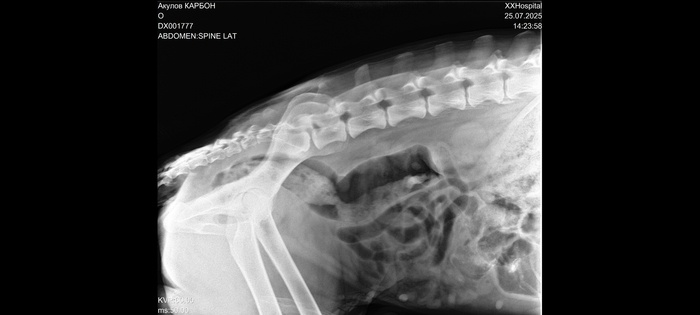

Сделали рентген и анализ крови.

Заключение - проблемы в позвоночнике.